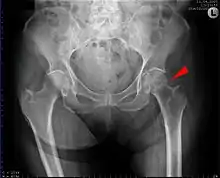

كسر مفصل الفخذ (كسر الورك) هو كسر في النهاية العلوية لعظم الفخذ (عظم طويل يمر عبر الفخذ)، بالقرب من مفصل الورك.

(كسر الورك) مصطلح يستخدم عادة للإشارة إلى أربعة أنواع مختلفة من الكسور. في كثير من الأحيان يحدث نتيجة لهشاشة العظام، وفي الغالبية العظمى من الحالات، كسر الورك يكون نتيجة سقوط بسيط أو صدمة طفيفة في شخص له عظام ضعيفة بسبب هشاشة العظام. أما معظم كسور الورك التي تحدث لأشخاص لهم عظام طبيعية تكون نتيجة لصدمة عنيفة مثل حادث سيارة.

هناك عدة أنواع فرعية من الكسور تحدث حول مفصل الفخذ معروفة بالعامية باسم كسور الورك. وعلى الرغم من أن كسر الورك الحقيقي يشمل مفصل الفخذ، إلا أن الأربعة أنواع التالية من كسور عظمة الفخذ يشار إليها عادة ب (كسور الورك). ولكن الاختلافات بينها مهمه جدا لأن كل منها يعامل بطريقة مختلفة.

- كسر عنق عظمة الفخذ : (أحيانا كسر عنق عظم الفخذ، subcapital تحت الرأس ، أو كسر داخل كبسولة المفصل intracapsular) يدل على وجود كسر بجانب رأس عظمه الفخذ في الرقبة بين الرأس والنتوء الأكبر trochanter. هذه الكسور من الممكن أن تؤدي إلى تدمير التغذية الدموية إلى رأس الفخذ، يحتمل ان تسبب موت رأس عظمة الفخذ نتيجة انقطاع الدم عنها avascular necrosis. احدى التصنيفات المستخدمة على نطاق واسع وأنشئت بواسطة Garden and Pauwels.

- (Intertrochanteric) كسر ما بين النتوئين ترمز إلى كسر حيث يكون خط الكسر بين النتوء الكبير والنتوء الصغير greater trochanter and lesser trochanter على خط ما بين النتوئين intertrochanteric line. هذا هو النوع الأكثر شيوعا من 'كسر الورك' وفي هذا النوع يكون تطور المرض وشفاء العظم جيد بشكل عام إذا كان المريض في صحة جيدة.

الأشعة السينية على الفخذ المصاب عادة ما تجعل التشخيص واضح، وينبغي الحصول على صور أشعه أماميه خلفيه وجانبيه.